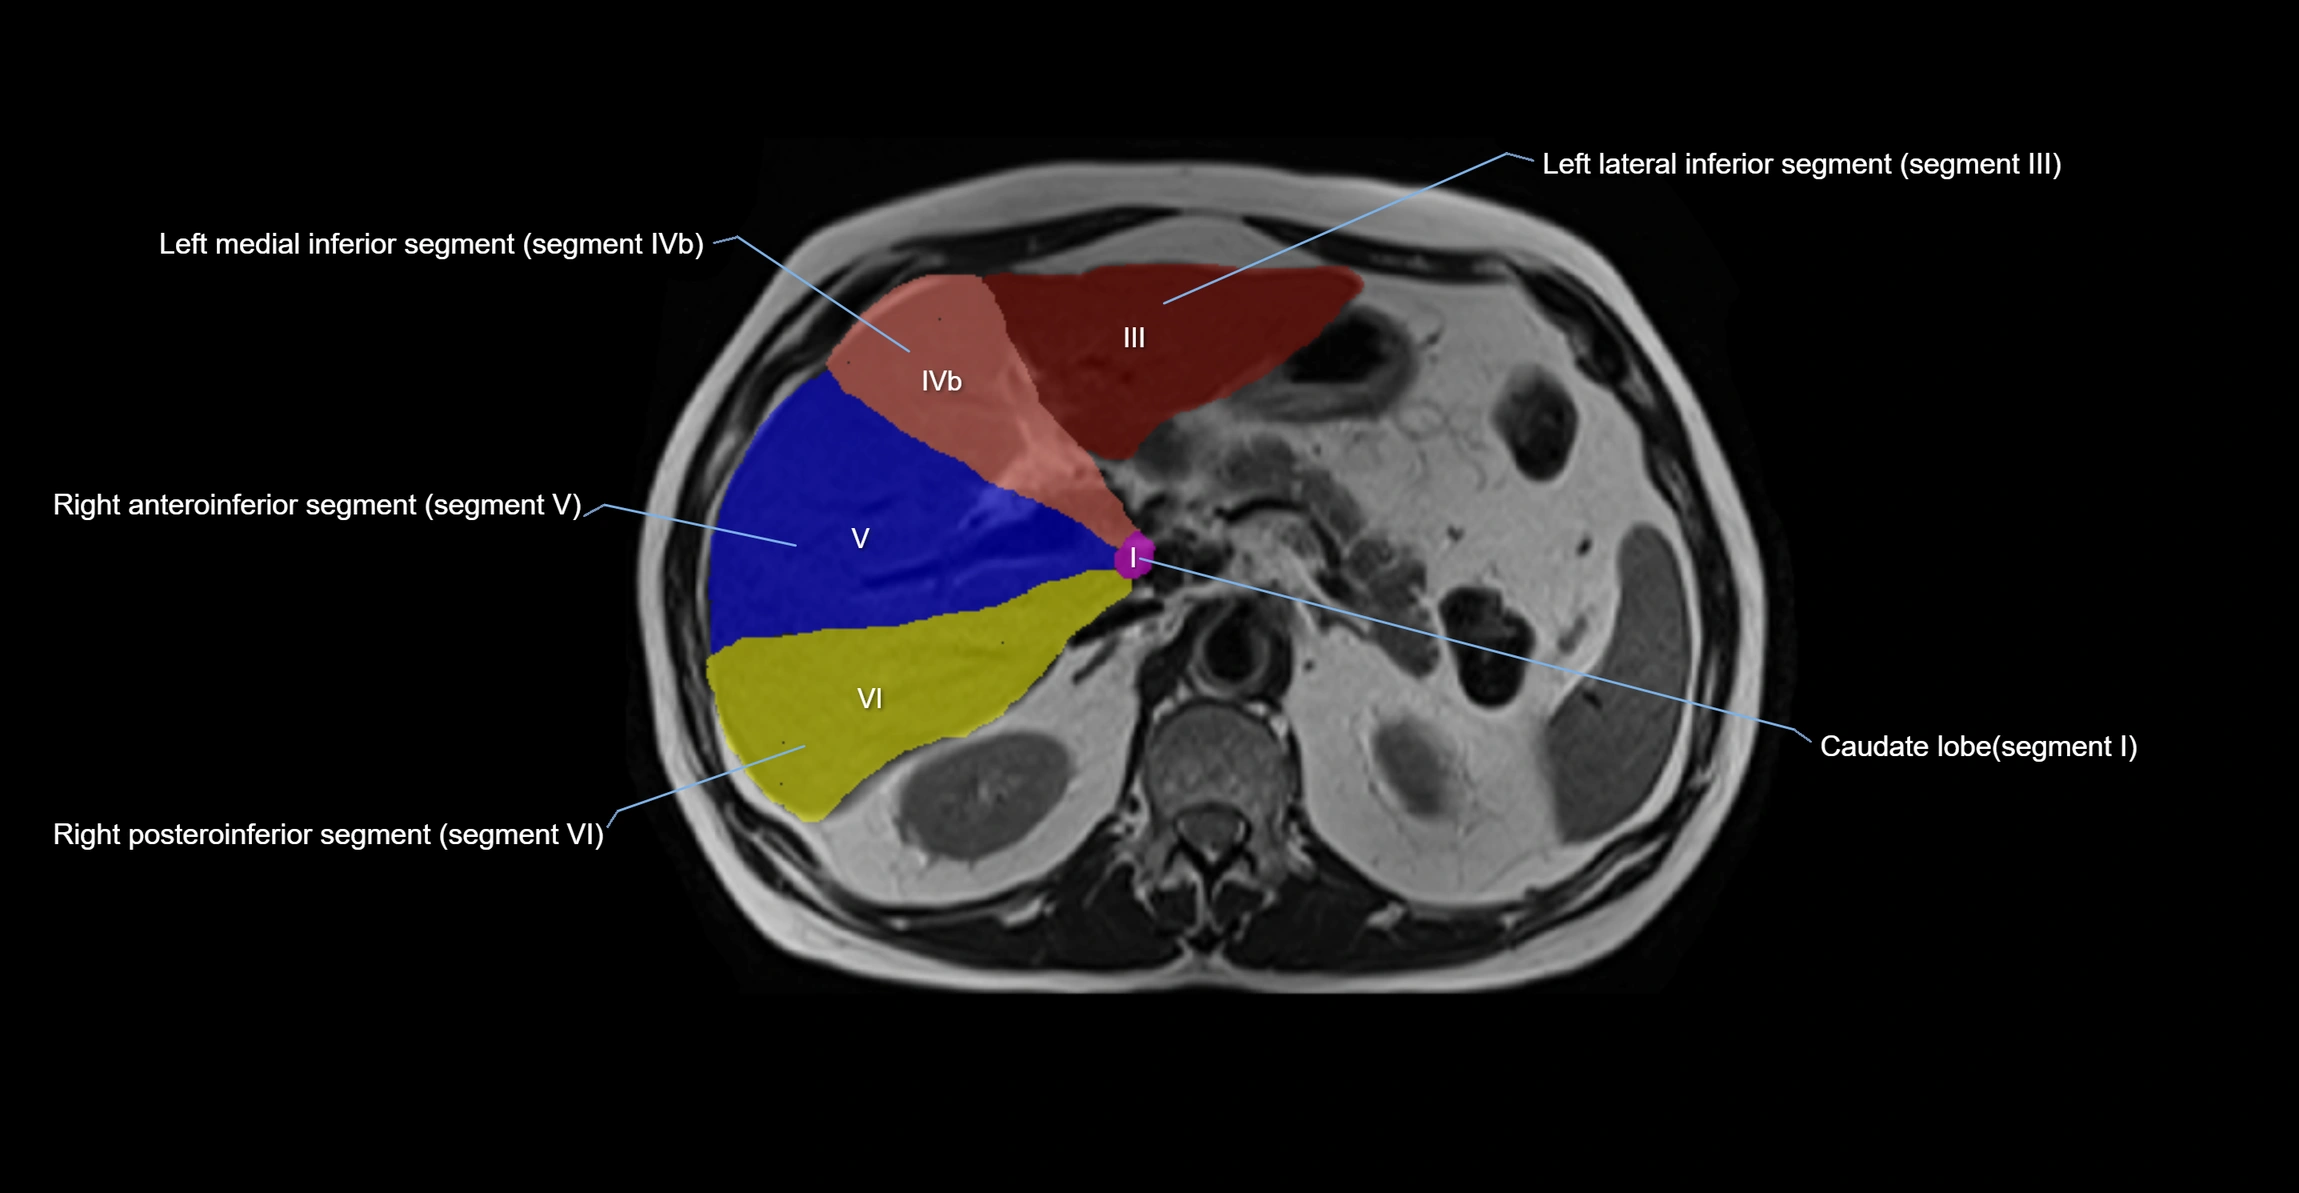

The caudate lobe of the liver is a distinct anatomical subdivision of the liver, designated as segment I in Couinaud’s classification. It lies on the posterior surface of the liver, between the fissure for the ligamentum venosum (left boundary) and the groove for the inferior vena cava (IVC) (right boundary). Superiorly, it is related to the posterior liver surface, and inferiorly it is separated from the left lobe by the porta hepatis.

The caudate lobe is unique because it receives dual portal venous and arterial inflow from both the right and left portal veins and hepatic arteries. It also has independent venous drainage directly into the IVC via multiple small hepatic veins, unlike other lobes that drain through the three main hepatic veins.

• Segment I (Couinaud classification)